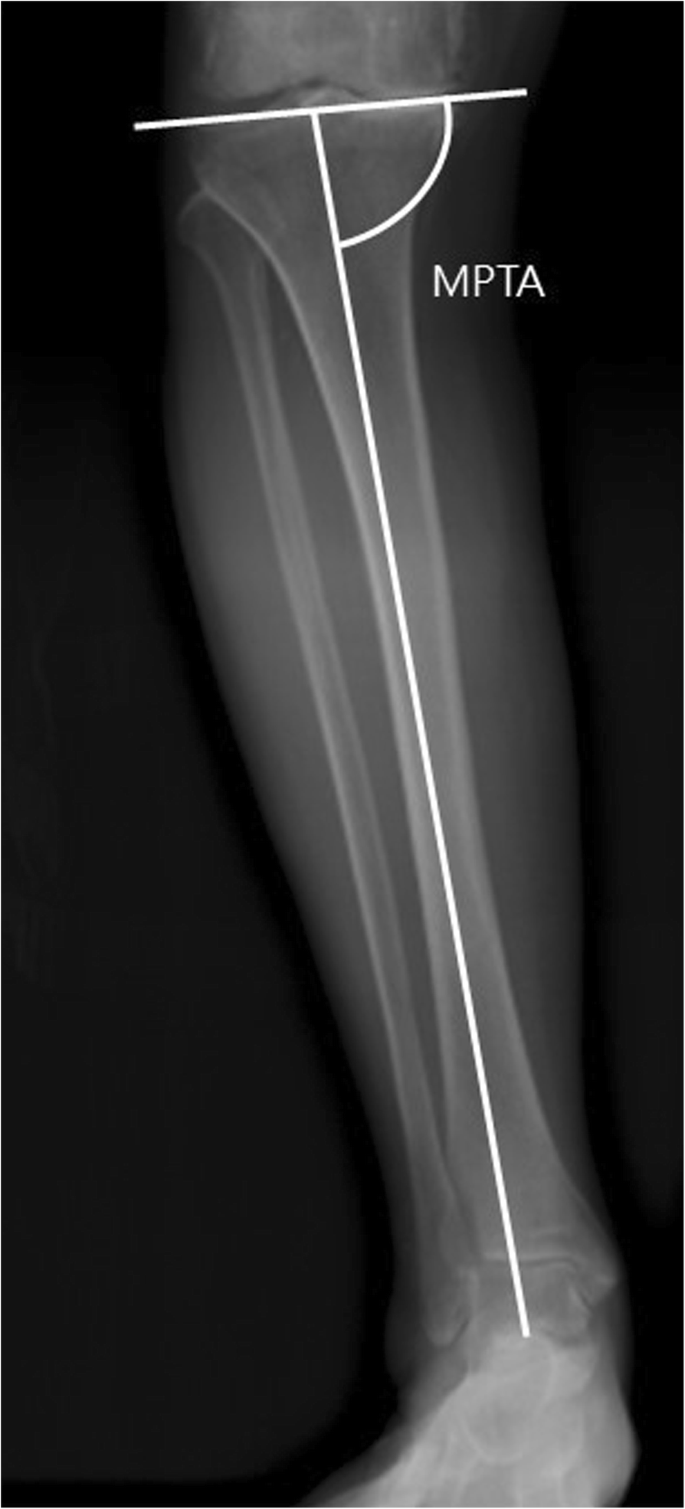

The MTPA determines the inclination of the tibial plateau, which is defined as the medial angle between the mechanical axis line of the tibia (line from the ankle center to the center of the tibial spines) and the knee joint line of the tibia [19]. (Fig. 3).